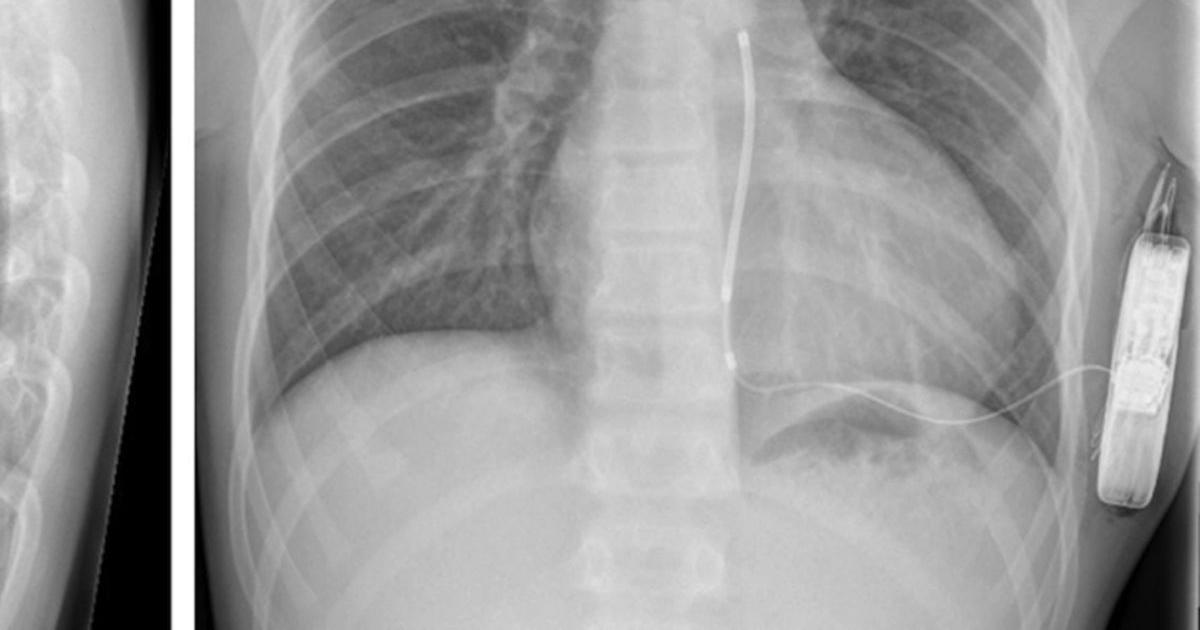

Implantable Cardioverter-Defibrillator

An implantable cardioverter-defibrillator (ICD) is a device implanted under the skin to monitor an individual's heart rate continuously. The device is connected to the heart with thin wires that detect dangerous changes in the heart rhythm. Upon detection of a heartbeat that is too rapid or too irregular, the ICD will deliver an electric shock to reset the heart's electrical system. The electric shock allows the heart to revert to a normal heartbeat. Because patients with long QT syndrome are at a much higher risk of experiencing life-threatening ventricular arrhythmias, implantable cardioverter-defibrillators are often utilized to prevent these dangerous cardiac events. The devices, which are relative in size to pocket watches, are powered by a battery and implanted in a pocket under the skin of the abdomen or the chest. Leads or small wires attached to the ICD are placed in different positions on the interior surface of the heart. The leads are the component of the device that allow it to monitor the activity of the heart, and they are the component that will deliver an electric shock to the heart tissues when it is necessary. This type of device is usually reserved for cases of long QT syndrome that cannot be effectively managed with medication and lifestyle changes.